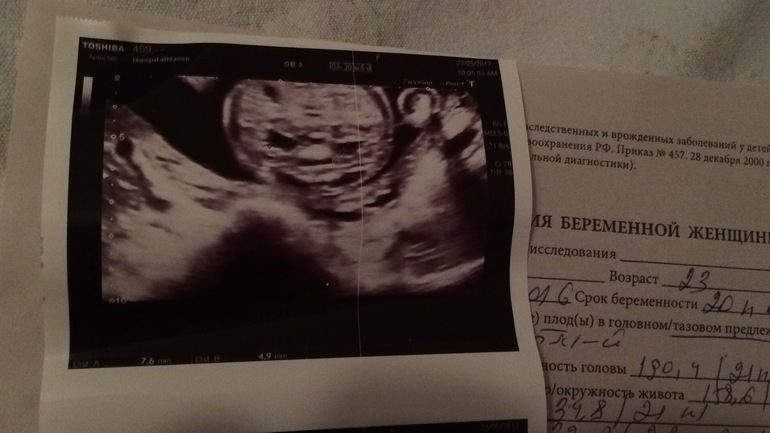

Неделю назад было второе скрининговое УЗИ,все в порядке,кроме увеличения члс почек!

В заключении:гидронефроз обеих почек ?

Размеры у нас 7,6;4,9